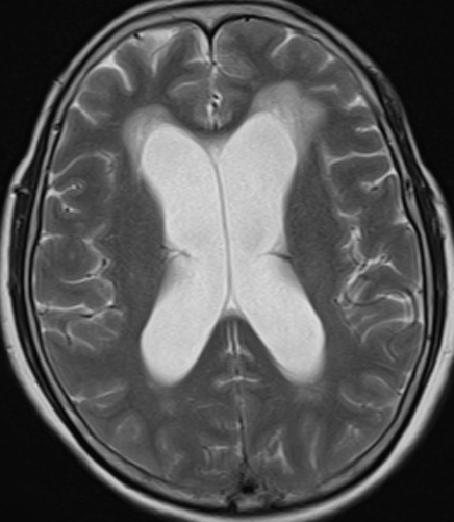

2013-8-2 MRI

2013-8-2 CT

腰穿脑压240